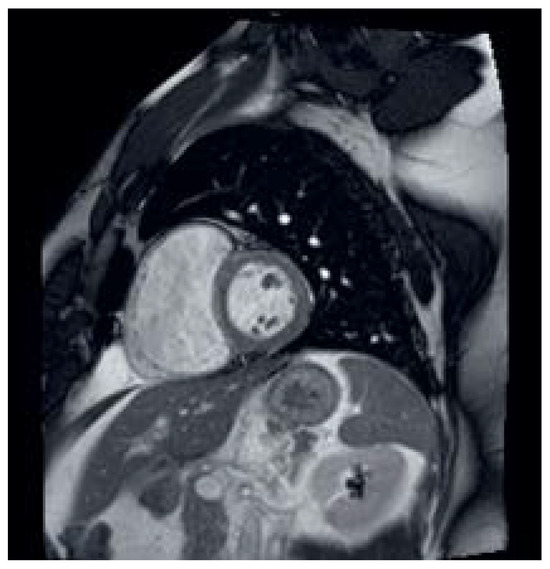

Surgical Correction of a Sinus Venosus Atrial Septal Defect with Partial Anomalous Pulmonary Venous Connections Using Cardiac Computed Tomography Imaging and a 3D-Printed Model

Sinus venosus atrial septal defects (SVASDs), concurrent with partial anomalous pulmonary venous connections (PAPVCs), are a rare congenital heart disease in dogs. Surgical correction is essential when clinical signs or significant hemodynamic changes are present. We aimed to report on the successful surgical [...] Read more.

Sinus venosus atrial septal defects (SVASDs), concurrent with partial anomalous pulmonary venous connections (PAPVCs), are a rare congenital heart disease in dogs. Surgical correction is essential when clinical signs or significant hemodynamic changes are present. We aimed to report on the successful surgical correction of an SVASD with PAPVCs, using a computed tomography (CT)-based customized 3D cardiac model. A 10-month-old male poodle was referred for corrective surgery for an ASD. Echocardiography confirmed a hemodynamically significant left-to-right shunting flow through an interatrial septal defect and severe right-sided heart volume overload. For a comprehensive diagnosis, a CT scan was performed, which confirmed an SVASD with PAPVCs. A customized 3D cardiac model was used for preoperative decision-making and surgical rehearsal. The defect was repaired using an autologous pericardial patch under a cardiopulmonary bypass (CPB). Temporary pacing was applied for sinus bradycardia and third-degree atrioventricular block. The patient recovered from the anesthesia without further complications. The pacemaker was removed during hospitalization and the patient was discharged without complications 2 weeks post-surgery. At the three-month follow-up, there was no shunting flow in the interatrial septum and the right-sided volume overload had been resolved. The cardiac medications were discontinued, and there were no complications. This report indicates the validity of surgical correction under CPB for an SVASD with PAPVCs, and the advantages of utilizing a CT-based 3D cardiac model for preoperative planning to increase the surgical success rate. Full article